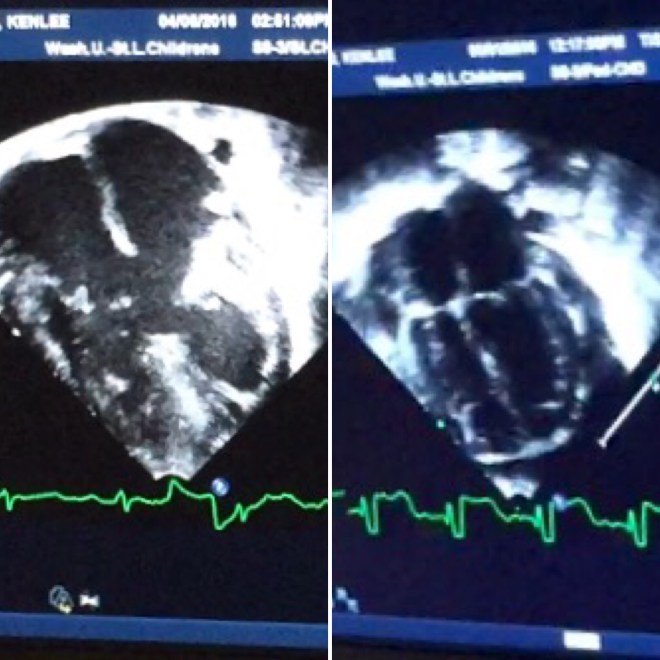

Below is a before and after of Kenlee heart. You can see on the left side there is an open area in the middle. Then on the right you can see the four chambers like a normal heart. Praise God that there is no more hole.